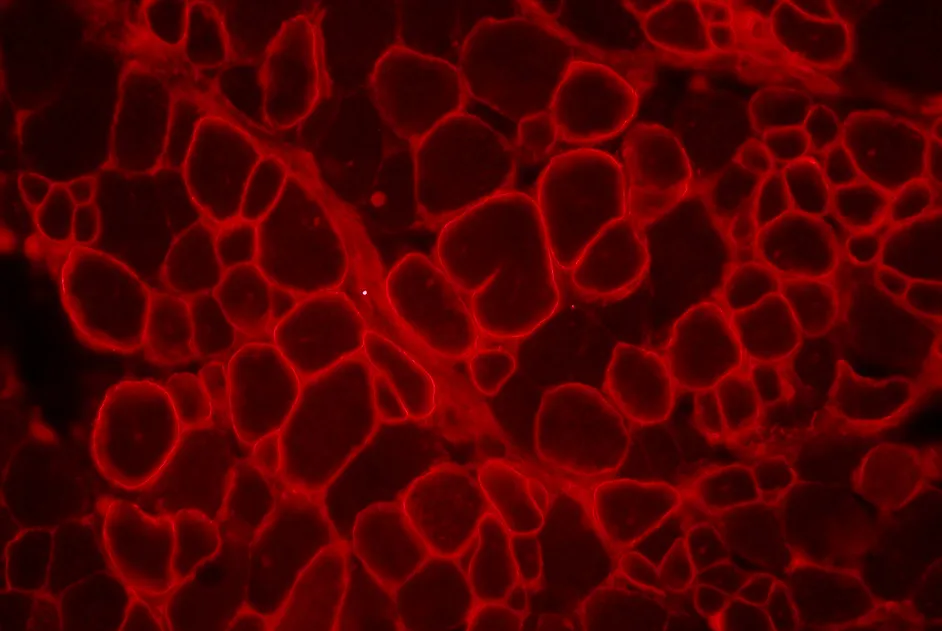

Les protéines MBNL1 et MBNL2 sont deux protéines régulatrices qui contrôlent l’activité de nombreuses autres protéines dans les cellules musculaires. Dans la DM1, la présence des agrégats nucléaires anormaux, en les séquestrant, les rend moins disponibles et moins actives, entrainant par ricochet de nombreuses perturbations dans les cellules musculaires.

Cette étude a montré que la chloroquine augmente la quantité de MBNL1 et MBNL2 disponibles et réduit les perturbations cellulaires caractéristiques de la DM1.